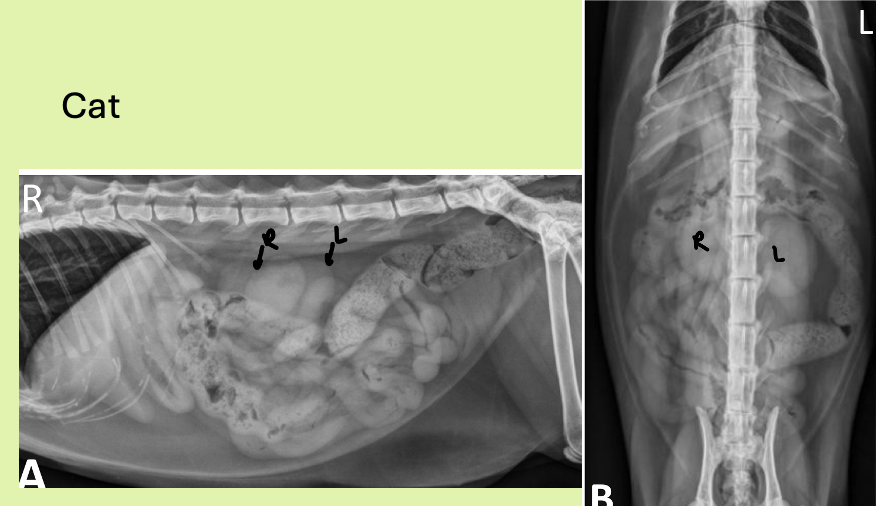

which view is best for eval of SIZE and shape of kidneys

VD

how are cat kidneys located differently from dog

more cd (same thing with right kidney more cr.)

shape of kidneys dog vs cat

dog - bean

cat - oval

what might you see in the renal pelvis region of cat that is different from dog kidneys

peripelvic fat